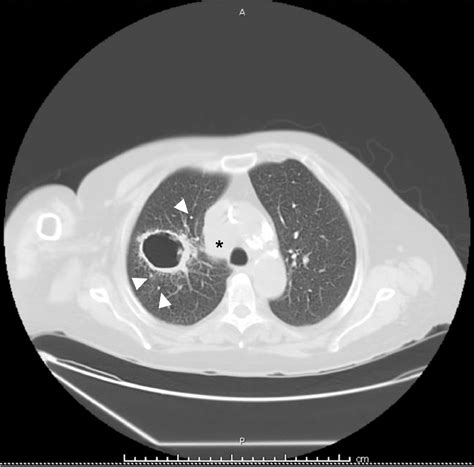

A cavitary lesion of lung is a significant radiological finding that requires careful medical evaluation. In clinical terms, a cavity is defined as a gas-filled space within a pulmonary consolidation, a mass, or a nodule. When a patient undergoes a chest X-ray or a computed tomography (CT) scan and receives this diagnosis, it often triggers immediate concern. However, understanding that these lesions can result from a wide spectrum of causes—ranging from common infections to serious malignancies—is crucial for both patients and healthcare providers to ensure accurate diagnosis and appropriate management.

At its core, a cavitary lesion of lung represents a localized area of the lung parenchyma that has been destroyed or excavated. This destruction often occurs when an area of diseased lung tissue undergoes necrosis—the death of cells—and the necrotic material is subsequently evacuated, usually through the bronchial tree. This leaves behind a hollow, air-filled void that appears distinctly on medical imaging.

Distinguishing Features on Imaging

Radiologists look for specific markers to help narrow down the diagnosis. The appearance of the cavity's wall, for instance, provides vital clues:

• Thick, Irregular Walls: These are more suggestive of malignancy (e.g., squamous cell carcinoma).

• Thin, Smooth Walls: Often point toward benign causes, such as a congenital cyst or a resolved infection (pneumatocele).

• Air-Fluid Levels: Highly indicative of a lung abscess, suggesting a collection of pus that has not yet been fully drained.